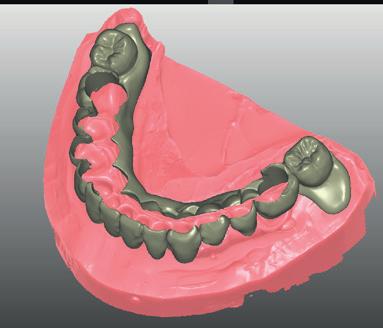

Flux numérique & C.F.A.O. 2 jours

• Réaliser des cas entièrement à l’aide du flux numérique : du wax-up numérique en passant par le guide d’imagerie puis le guide chirurgical jusqu’à la prothèse provisoire qui précède la prothèse d’usage.

• Combiner les différents examens numériques pour réaliser des plannifications implantaires et prothètiques.

• Flux numérique et plans de traitements.

• Le différentes étapes du process numérique.

• Design de guides chirurgicaux, de prothèse provisoire et définitive.

• Les moyens de production : usinage, impression 3D, ... .

Bridge provisoire immédiat sur implants.

Scanner facial et wax-up virtuel.

Scanner intra-oral (empreinte optique). Guide